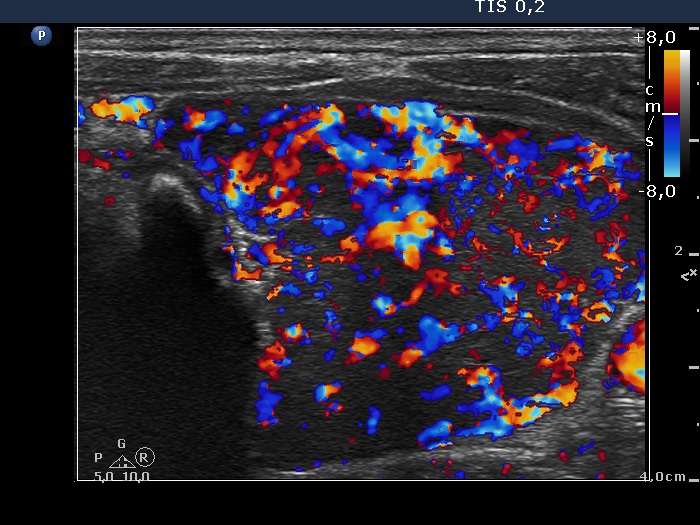

Consecutively operated patients with autoimmune thyroid disease - case 26 (1674) (ultrasonographic picture 8)

Left lobe, transverse view, color Doppler mode. The vascularization is significantly increased.